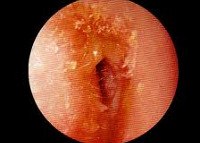

При отоскопии выявляют покраснение кожи слухового прохода, инфильтрацию; просвет слухового прохода сужен и заполнен гнойно-эпидермальными массами (скудные выделения с запахом наиболее характерны для синегнойной палочки).

Отоскопия • Фурункул наружного слухового прохода — ограниченный инфильтрат, суживающий просвет слухового прохода • Разлитой (диффузный) наружный отит •• Острая форма. Гиперемия, инфильтрация кожи перепончато – хрящевой части слухового прохода, сужение просвета слухового прохода различной степени. В глубине его можно увидеть кашицеобразную массу, состоящую из десквамированного эпидермиса и гноя с резким гнилостным запахом. Барабанная перепонка умеренно гиперемирована и покрыта слущенным эпидермисом •• Хроническая форма. Утолщение кожи слухового прохода и барабанной перепонки •• Грибковое поражение (отомикоз). Слуховой проход сужен на всём протяжении как в костном, так и в перепончато – хрящевом отделе вследствие инфильтрации кожи. Барабанная перепонка доступна осмотру ••• При поражениях плесневыми грибами рода Aspergillus патологическое отделяемое в наружном слуховом проходе напоминает промокательную бумагу. Цвет отделяемого чёрно – коричневый при инфицировании грибами Aspergillus niger, желтоватый или зелёный — Aspergillus flavus, Aspergillus graneus, серо – чёрный — Aspergillus fumigatus ••• При этиологической роли дрожжеподобных грибов рода Candida отоскопическая картина напоминает мокнущую экзему наружного уха. Патологическое отделяемое в слуховом проходе имеет вид беловатых или желтоватых корочек, отрубевидных чешуек или казеозных масс, закрывающих просвет слухового прохода. Процесс часто распространяется на ушную раковину и заушную область.